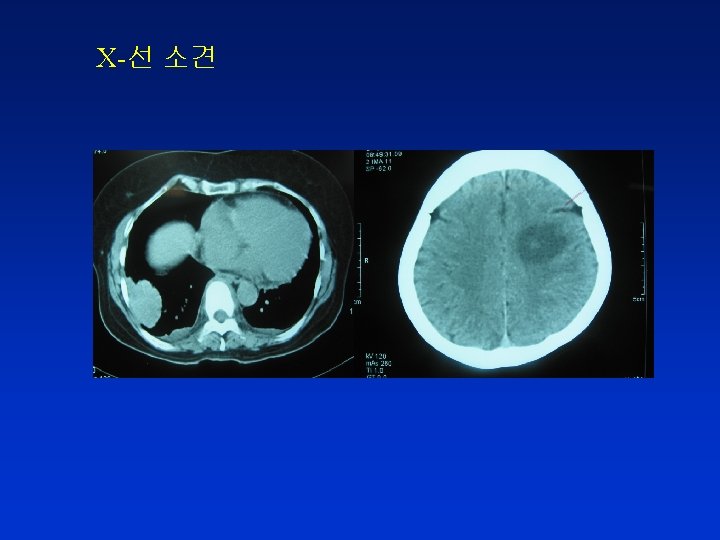

증례 2 48세 여자 진단 : adenocarcinoma of lung 주소 : vague headache for 1 month 현 병력 : 2개월 전 Lung cancer with spine metastasis 진단 spine radiation therapy 받은 후 chemotherapy 위하여 입원 이학적 소견 : 신경학적 검사 – 정상 검사실 소견 : CBC : Hb 9. 0 g/dl, Hct 29%, WBC 3, 900, PLT 250, 000/ Blood chemistry : WNL

진 단 Lung cancer with brain metastasis

치 료 1) Radiation therapy 300 c. Gy/day, for 10 days 2) Dexamethasone 5 mg PO, every 6 hours to prevent radiation induced edema